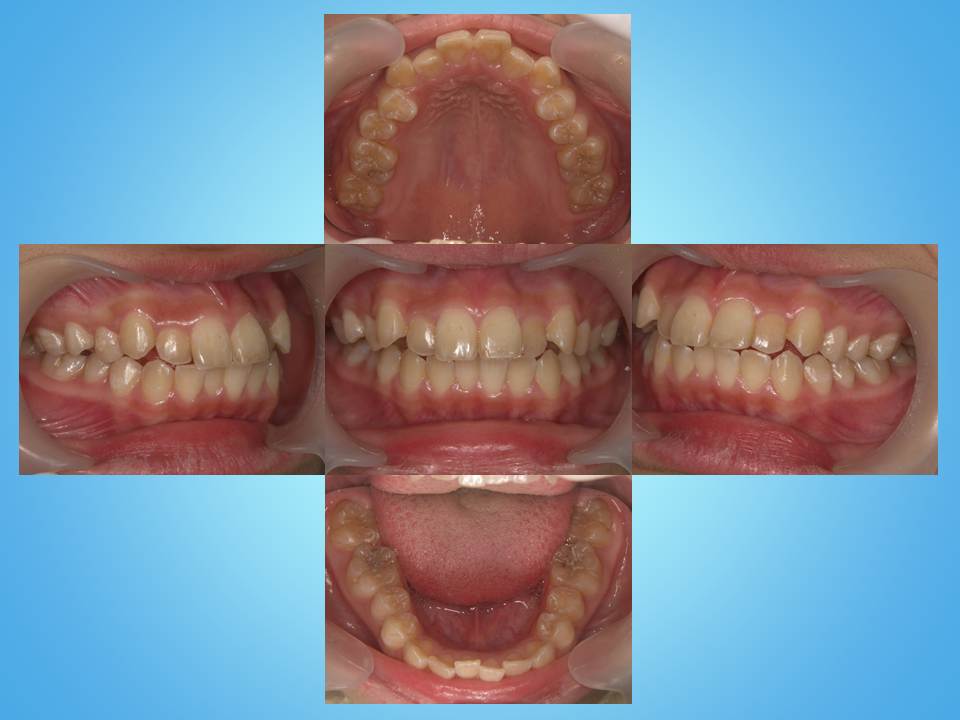

↑術前です。上下とも前歯の並びに問題があります。

↑ 20ヵ月目で装置を外すことができました。

↑ 歯並びが良くなったことで唇のラインも綺麗に整いました。